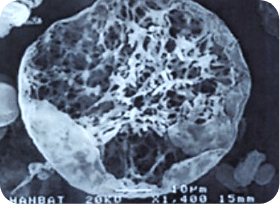

< 다공성 원형구조 미세분자 >

생분해성으로 체외로 모두 배출되기 때문에 체내에 잔존물이 거의 남지 않습니다.

긴 유지기간

둥글게 생긴 다공성

망상구조의 입자가

콜라겐 재생효과를

비교적 오래 유지 -